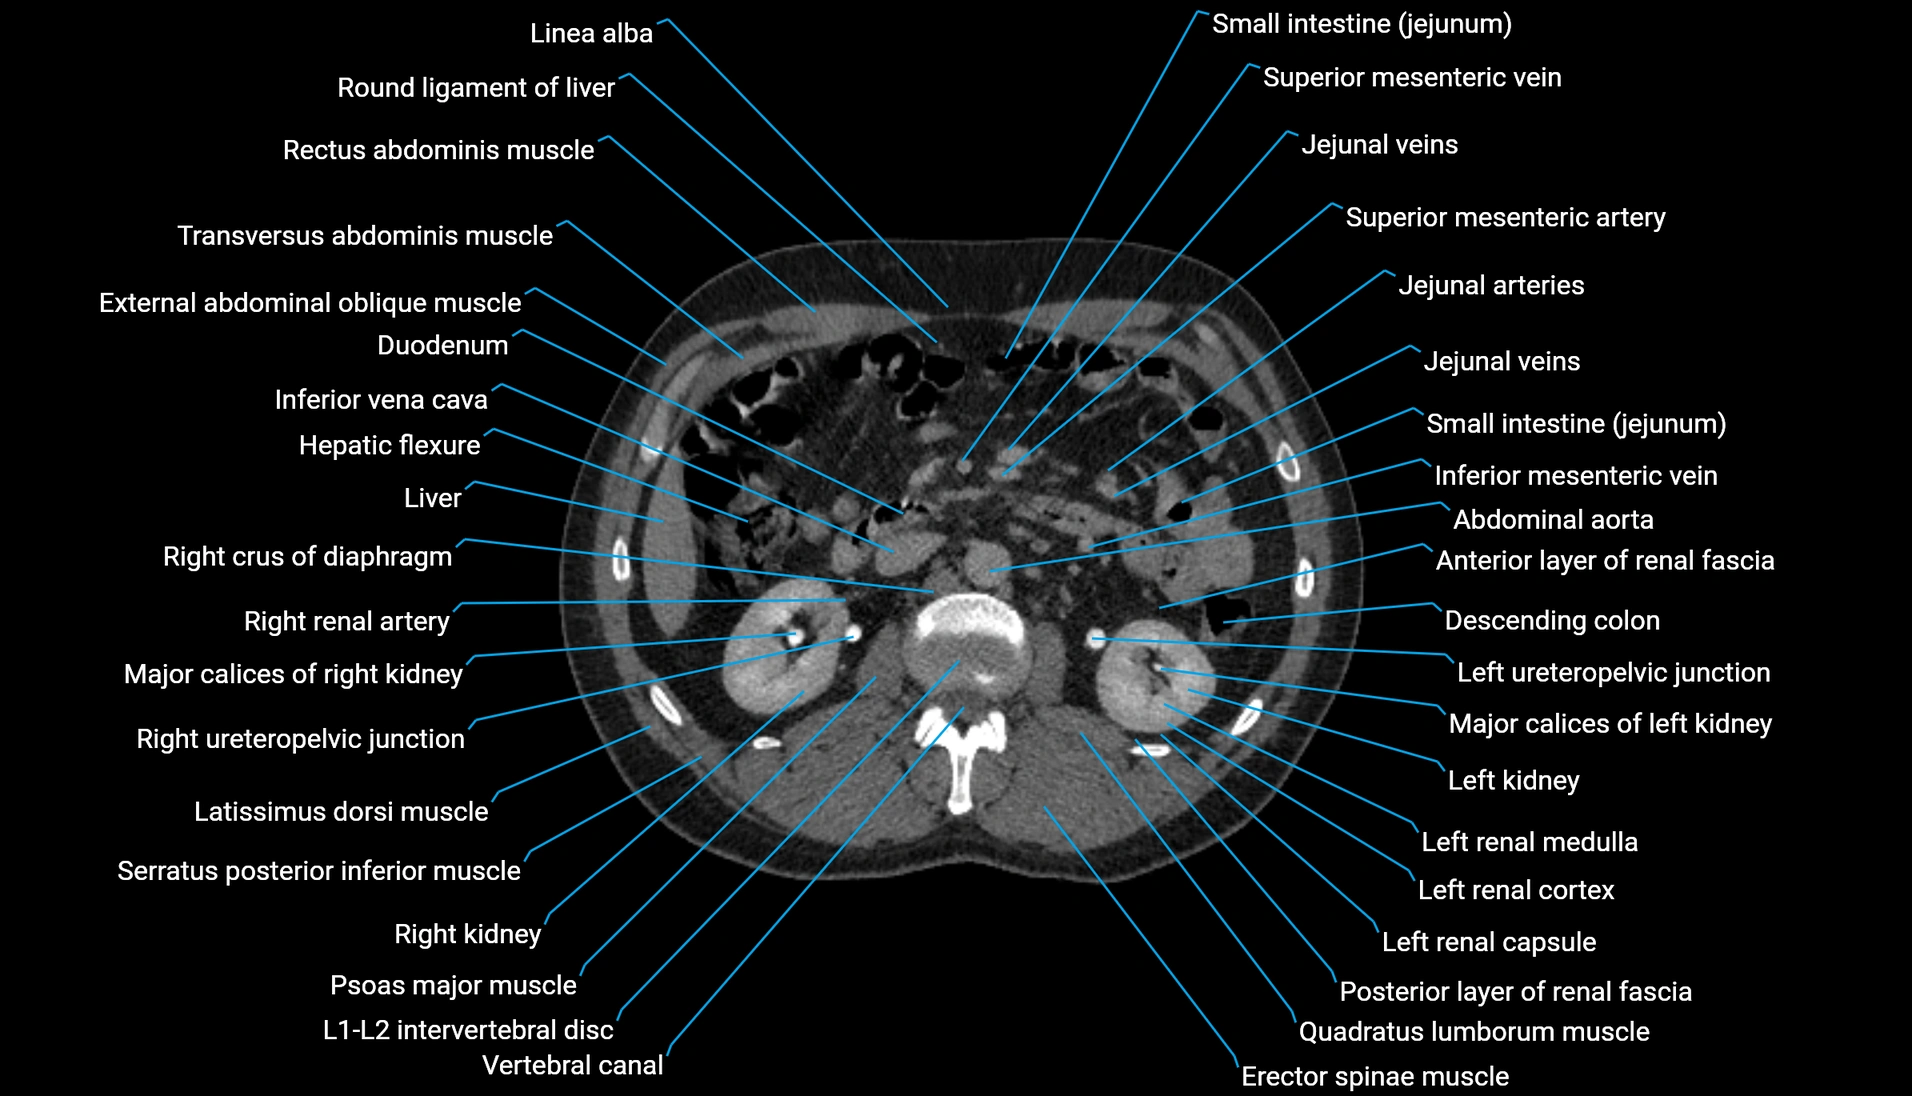

CT Appearance

Non-contrast CT:

-

Demonstrates cortical bone of acetabular rim in excellent detail

Detects fractures, dysplasia, retroversion, or bony overcoverage (pincer impingement)

3D reconstructions used in preoperative hip surgery planning

CT VRT 3D image

CT image